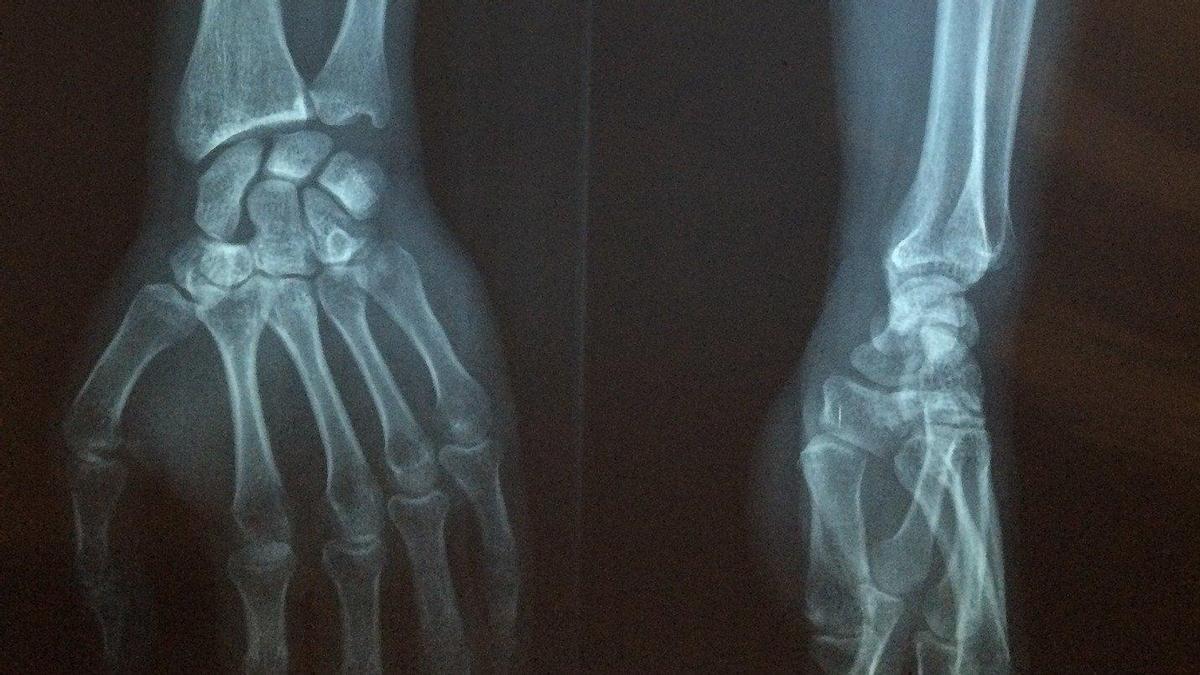

En la investigación se ha contado con la intervención del doctor Damián Mifsut -del mismo Grupo de Investigación y jefe de sección del Servicio de Cirugía Ortopédica y Traumatología del Hospital Clínico de Valencia-, el doctor Antonio Cano -jefe del servicio de Ginecologíía y Obstetricia del Clínico- y de Clara Pertusa, investigadora predoctoral del grupo. A pesar de que son patologías de inicio tardío, la osteoporosis y la artrosis muestran una elevada prevalencia en la población debido al aumento en la esperanza de vida, que producen desde dolor hasta deformidad ósea y fracturas, disminuyendo la calidad de vida de quienes las padecen.

Su origen puede deberse tanto a factores genéticos como ambientales y de estilo de vida y su mayor incidencia se encuentra en el grupo de mujeres postmenopáusicas, debido a los cambios en los niveles de hormonas que se producen durante esta etapa. La osteoporosis tiene como principal consecuencia la fractura ósea por fragilidad, debido a la baja masa ósea y deterioro de la microarquitectura del hueso que caracterizan esta enfermedad.

En la actualidad, causa más de 8,9 millones de fracturas cada año en todo el mundo, y su prevalencia está aumentando en paralelo con la creciente esperanza de vida (22 % de las mujeres mayores de 50 años en la UE). Por su parte, la artrosis genera dolor articular y deterioro funcional y puede provocar cambios patológicos como destrucción del cartílago articular, rigidez y formación de osteofitos (espolones óseos). Afecta a más de 40 millones de personas en toda Europa y, con el aumento de la longevidad, se prevé que se convierta en una de las principales causas de discapacidad en todo el mundo.

El objetivo de la investigación era buscar biomarcadores de la osteoporosis y la artrosis, según las fuentes, que indican que los microARNs han mostrado su potencial como biomarcadores en numerosas patologías. El actual estudio partía de otro anterior del mismo grupo en el que se analizaba y comparaba la expresión de 179 microARNs séricos en mujeres que habían sufrido una fractura de cadera osteoporótica y en mujeres sometidas a la implantación de una prótesis de cadera debido a coxartrosis severa.

La investigación actual analiza la utilidad como biomarcadores de osteoporosis y de artrosis de 4 microARNs que en el trabajo previo aparecían diferencialmente expresados entre grupos. Para ello, se midieron mediante PCR cuantitativa y se compararon estadísticamente los niveles de estos 4 microARNs en el suero sanguíneo de un total de 100 mujeres postmenopáusicas, divididas en 3 grupos: control (sin patología ósea), con coxartrosis severa y con fractura de cadera.

El hallazgo más importante del estudio, desarrollado durante cinco meses, muestra que el miR-497 circulante puede representar un biomarcador significativo de coxartrosis, un hallazgo prometedor que podría contribuir al futuro diagnóstico en etapa temprana de esta enfermedad, según las fuentes.